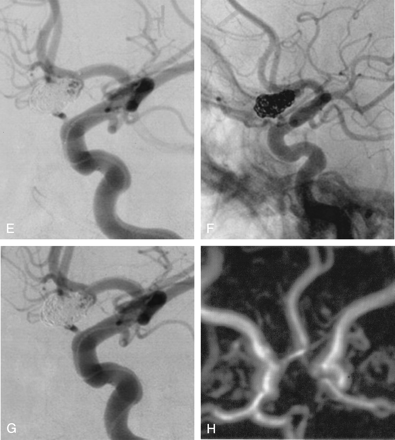

A 37-year-old woman (patient 12) presented with a SAH (HH grade I), and conventional angiography (Fig 2A) revealed an anterior communicating artery aneurysm. The patient was treated by selective embolization with Orbit coils alone. Five complex coils were delivered within the aneurysm lumen, including a 9 mm/25 cm coil (Fig 2B), a 7 mm/21 cm coil (Fig 2C), a 5 mm/15 cm coil (Fig 2D), a 3 mm/3 cm coil (Fig 2E), and a 2 mm/2 cm coil. Conventional angiograms (Figs 2F, -G) at the end of the procedure showed a neck remnant. The patient made an excellent recovery and was discharged 12 days after the treatment. MRA at 6 months showed complete occlusion of the aneurysm (Fig 2H).

Selective embolization with complex Orbit coils only: five coils were delivered within the aneurysm lumen including a 9 mm/25 cm coil (B), a 7 mm/21 cm coil (C), a 5 mm/15 cm coil (D), a 3 mm/3 cm coil. (E), and a 2 mm/2 cm coil.

Conventional nonsubstracted (F) and substracted (G) angiograms at the end of the procedure show a neck remnant.

Follow-up MRA (H) at 6 months shows a complete aneurysm occlusion.